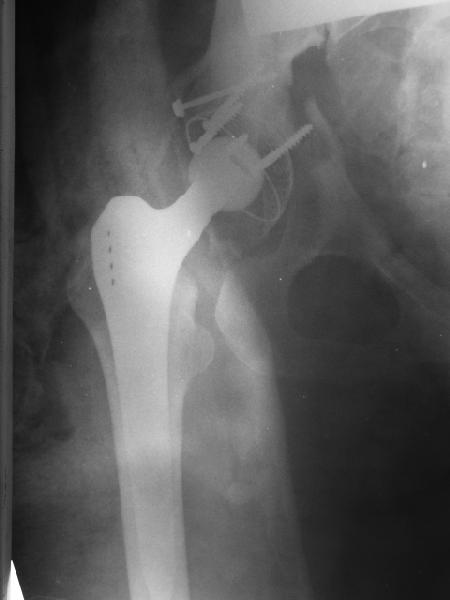

Обратились коллеги из городской больницы N36. Женщине 39 лет по поводу диспластического коксартроза около года назад выполнено эндопротезирование правого тазобедренного сустава. Вчера ехала на госпитализацию на протезирование второго сустава, и попала в аварию.

Получила поперечный перелом правой вертлужной впадины (снимок прилагается) с переломом ветвей лонной кости на другой стороне (inletview также в приложении), а также поперечный перелом дистального метафиза бедра на этой же стороне. Что посоветуете в отношении протеза и впадины? Спасибо заранее.

A colleague of mine from another hospital requests opinion. A female 39 years old was operated ~1 year ago - right side THA for hypoplastic hip. Yesterday she was going to the hospital for THA ofthe second hip but got involved in a car accident.She admitted with right acetabular and left rami fractures (images attached). Also trasverse fracture of the right distal femur.Seeking your advice regarding the acetabular fracture. THX!

Ножка Алтимед, а чашка цементая???? Хороший гибрид. Насколько позволяет рентгенограмма, можно судить, что чашка стабильна (за счет цемента и арматуры в виде винтов). Нужен постельный режим не менее 6 недель.

Ситуация редкая и нестандартная. Складывается впечатление, что эндопротез вертлужной впадины стабилен. Я бы выполнил остеосинтез перелома в/впадины реконструктивной пластиной. Эти переломы срастаются хорошо.

Установлена RM-чашка бесцементная,ножка тип Цвайммюллер производства Мathys,сделана костная пластика.В настоящее время необходим остеосинтез реконструктивной пластиной без удаления чашки,так как чашка стабильна.